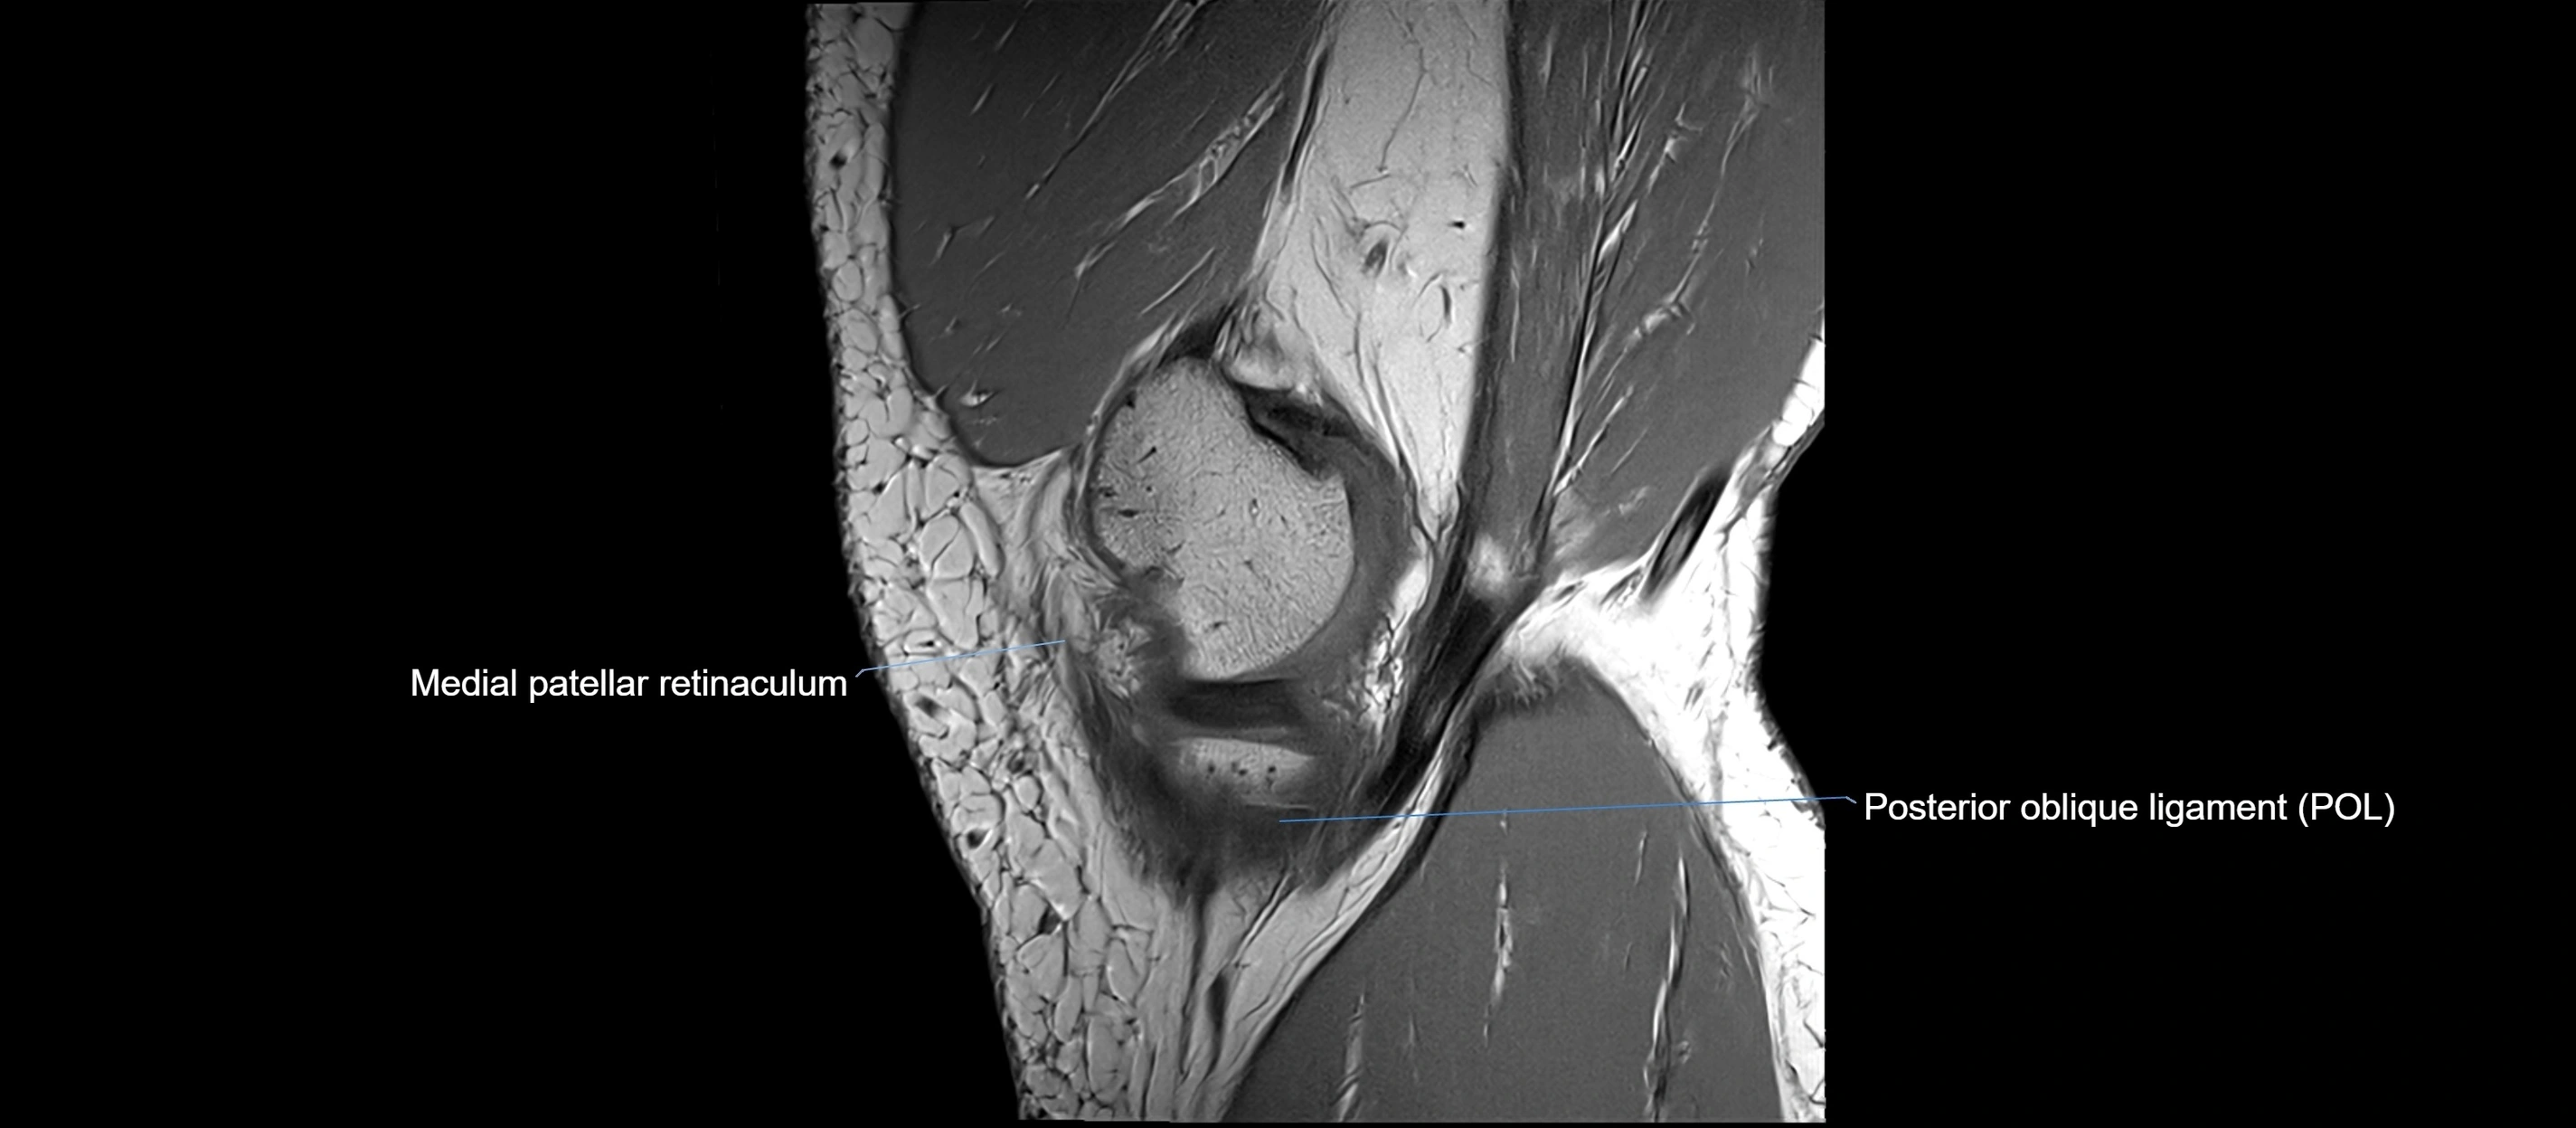

MRI images

image